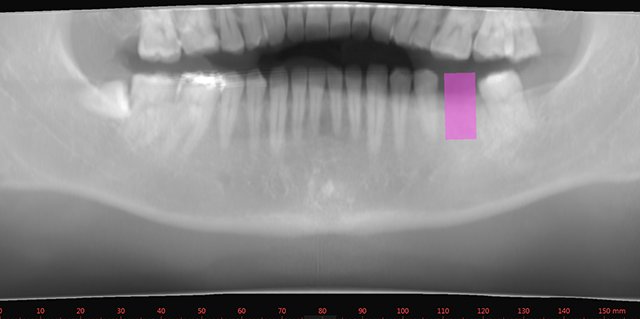

BrainVoyager starts by automatically assembling images into 2D and 3D functional and anatomical multi-slice projects.

Segmentation

Segmentation of tissue (e.g., isolating the brain, differentiating gray and white matter) is performed using region-growing methods, filter operations as well as the application of 3D templates. Using the mouse it is very easy to explore a 3D volume with superimposed pseudocolor-coded statistical maps in a four-window representation showing a sagittal, coronal, transversal and oblique section. Based on a (segmented) 3D data set a three-dimensional reconstruction of the subjects' head and brain can be calculated and displayed from any specified viewpoint using volume or surface rendering.